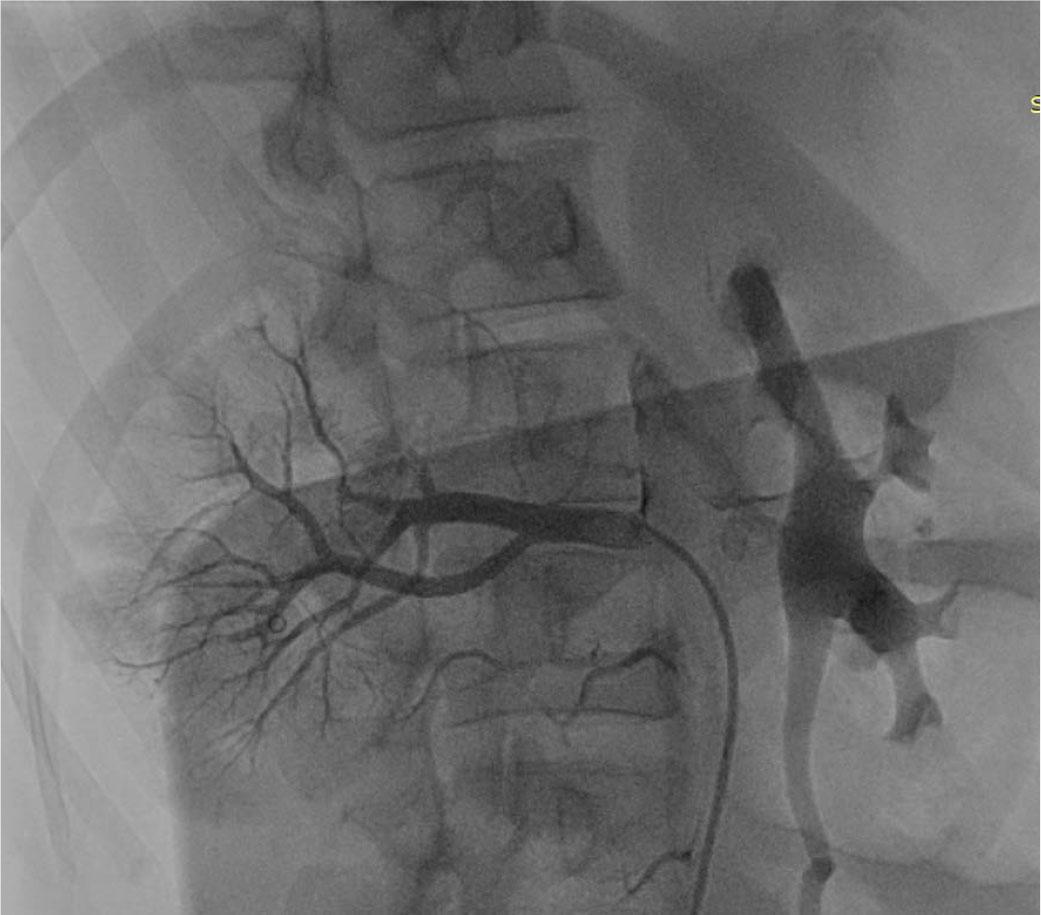

FIGURE 2.